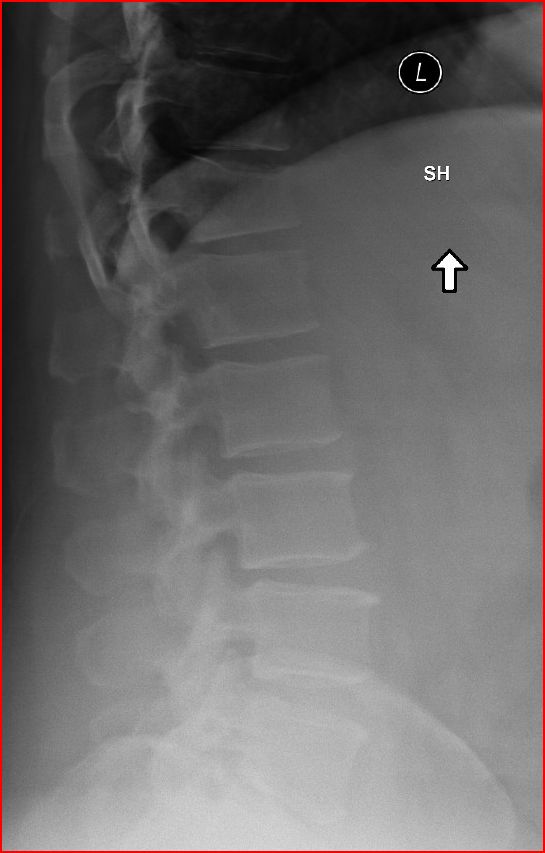

Here are a couple of shots from todays x-ray.

The pictures do not reflect the fracture as well as the film from the hospital. I’ll try to get that film and place it here.